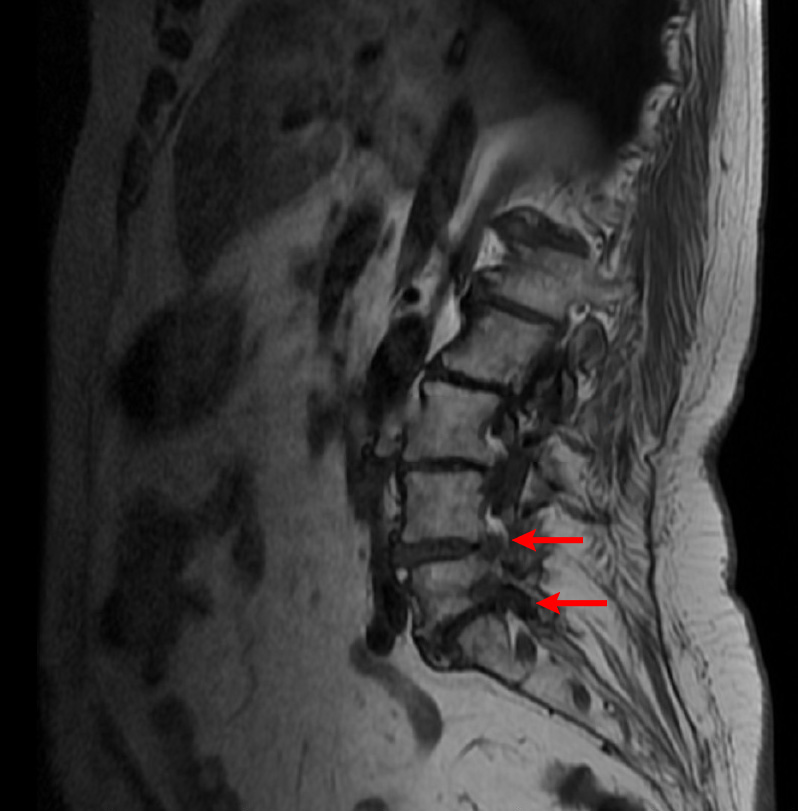

Ασθενής με 2 πολύ μεγάλες δισκοκήλες

Ασθενής 75 ετών με αδυναμία βάδισης λόγω έντονης οσφυαλγίας από έτους. Η αιτία είναι δύο μεγάλες δισκοκήλες που πιέζουν τις εξερχόμενες ρίζες των νεύρων. Με τοπική αναισθησία τοποθετήθηκαν 2 βελόνες στα στα  επίπεδα Ο4-05 και Ο5-Ι1 και έγινε  εισαγωγή μείγματος αναλγητικών. Άμεση ανακούφιση με αποτέλεσμα που διατηρείται 1 χρονο μετά.